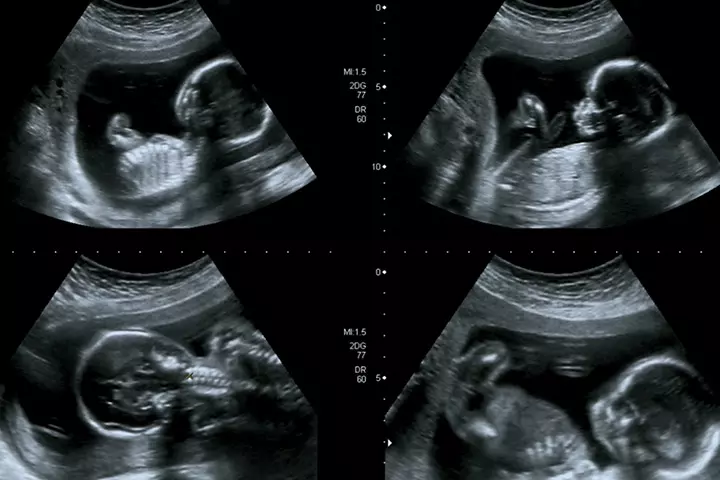

رشد جنین در ماه سوم بارداری

سه ماهگی بارداری، که هفتههای نهم تا دوازدهم را در بر میگیرد، مرحلهای کلیدی در تکامل جنین به شمار میرود. در این دوره، رشد سریع بافتها و شکلگیری دقیق اندامها ادامه مییابد و جنین وارد مرحلهای میشود که به لحاظ ظاهری شباهت بیشتری به نوزاد پیدا میکند. بسیاری از سیستمهای بدن هم در این ماه آغاز به فعالیت یا تکامل میکنند. در ادامه، اطلاعات بیشتری درباره رشد جنین در این ماه در اختیارتان میگذاریم.